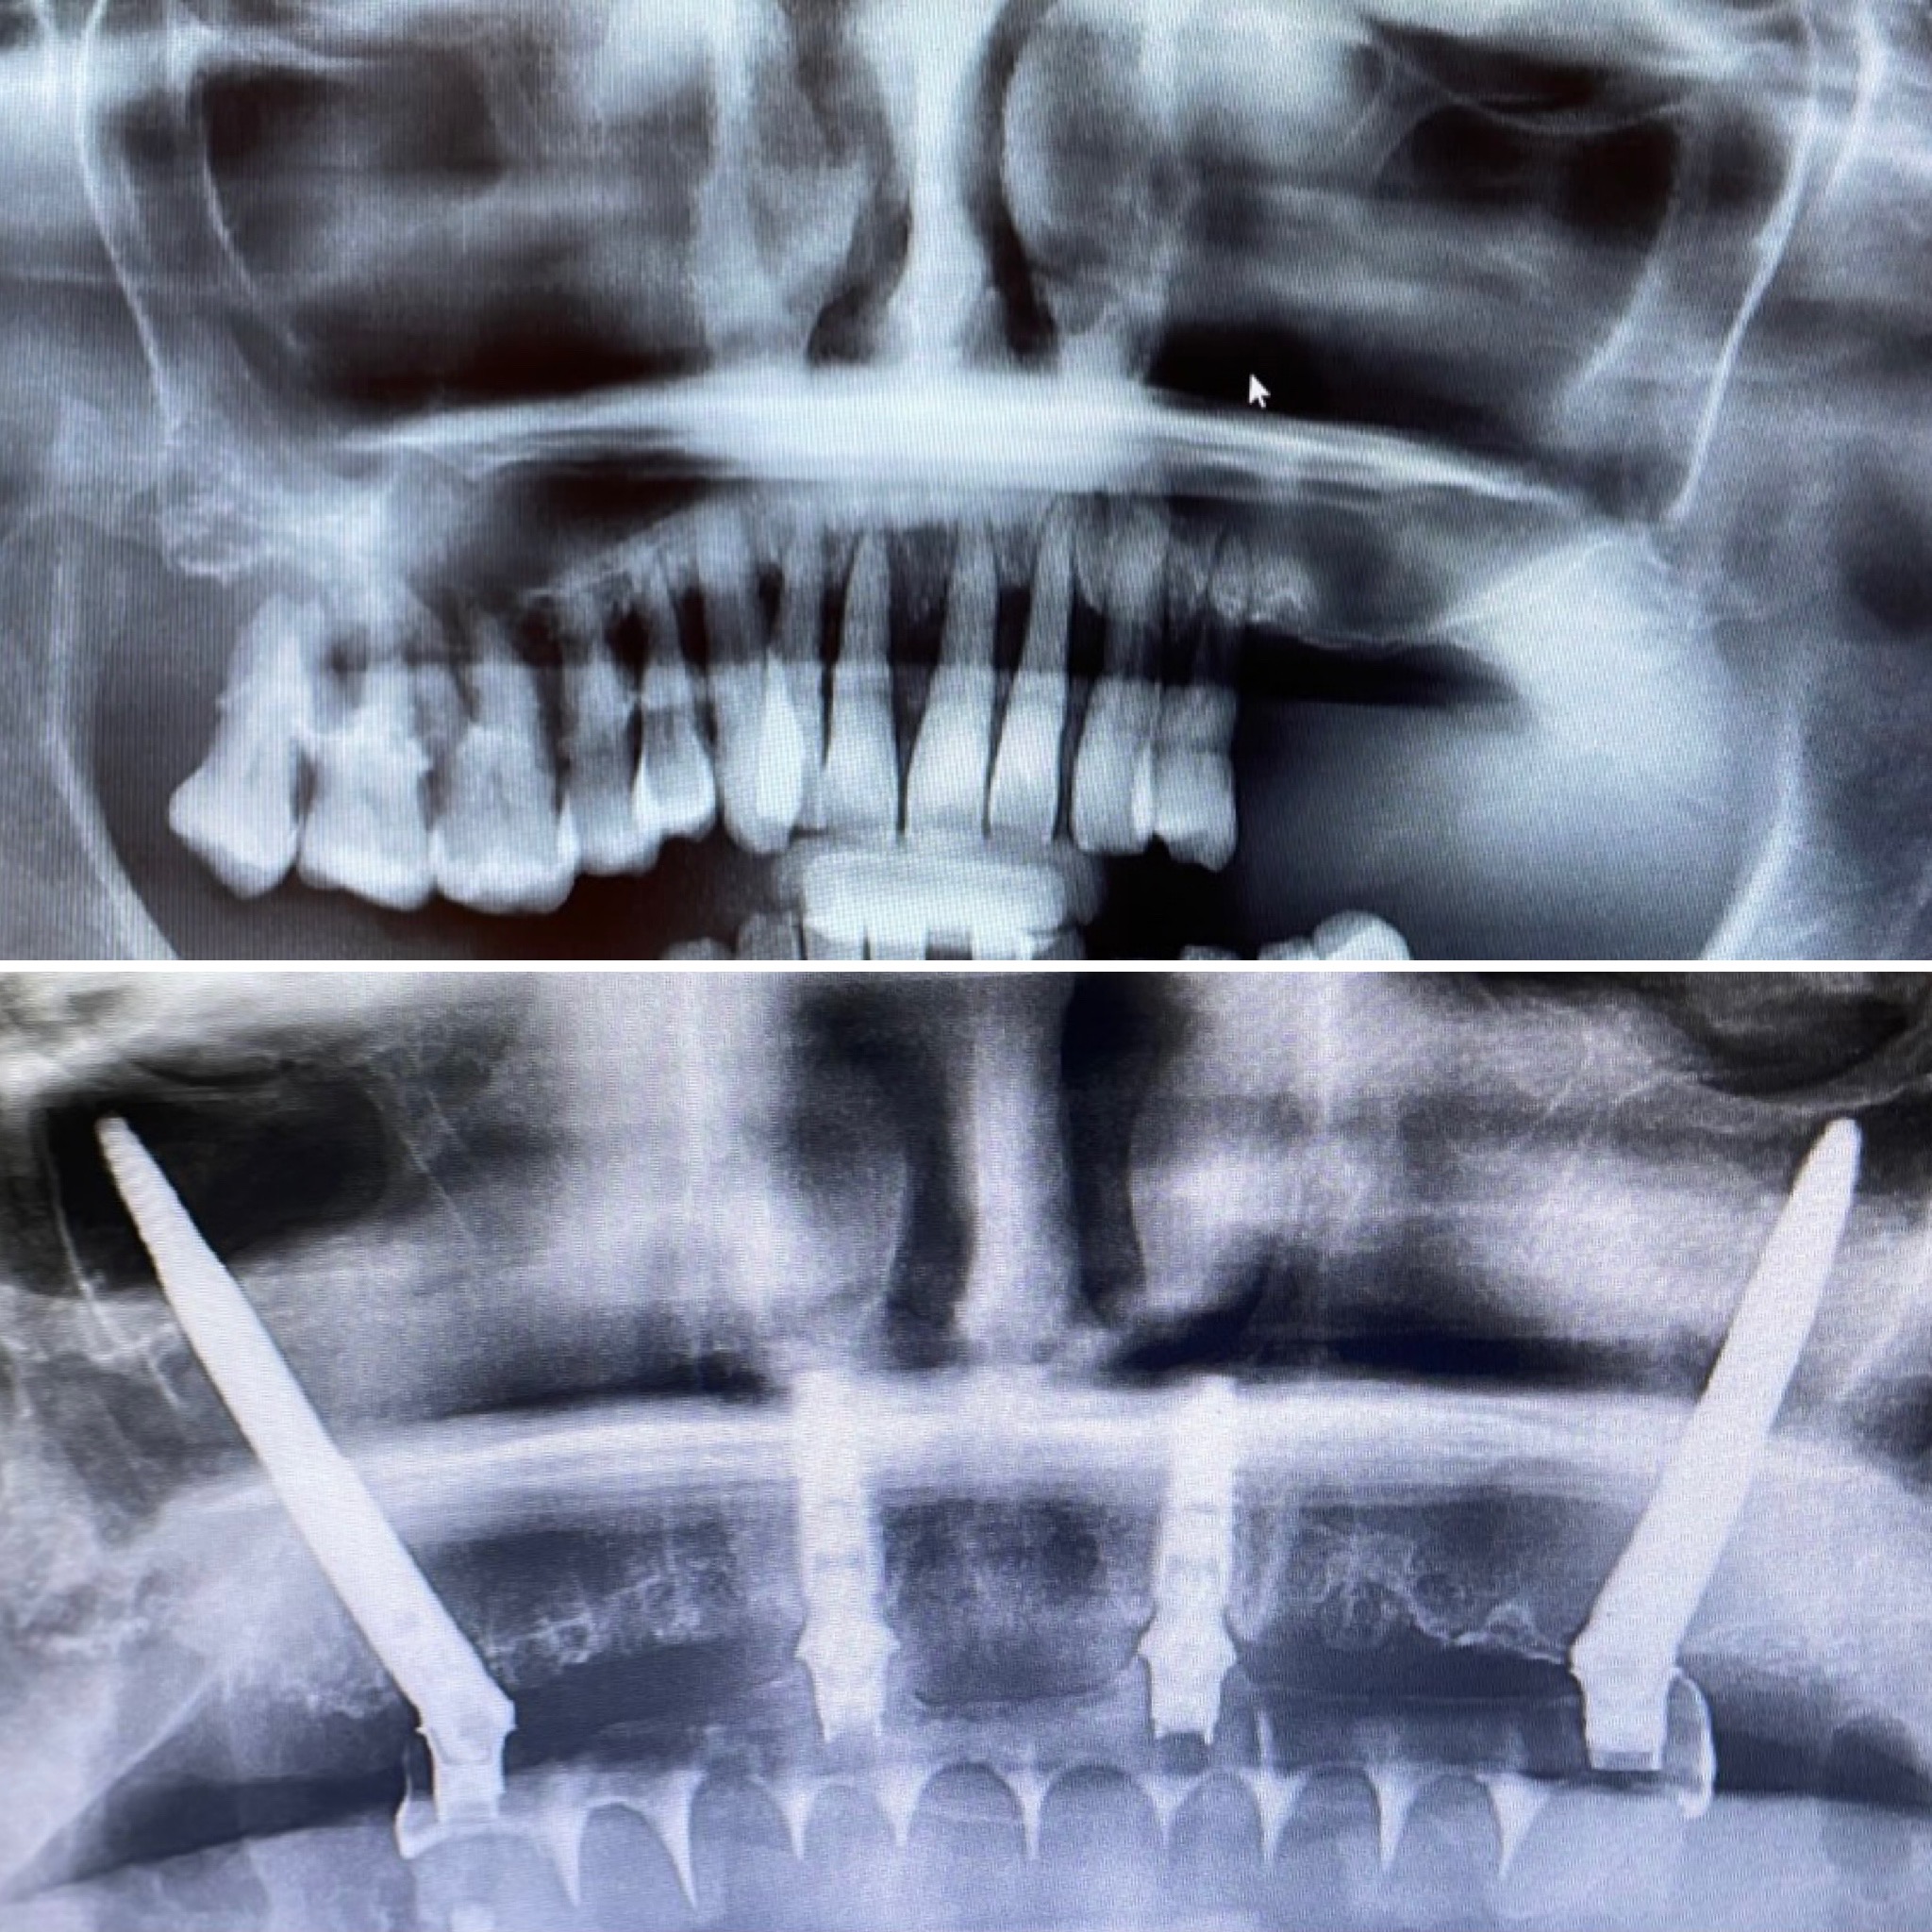

All on four nobel Biocare

El All on Four es un técnica avanzada de implantologia con amplia evidencia científica con la que somos capaces de rehabilitar de manera completamente fija casos con perdida ósea severa, sin injertos de hueso y en menos tiempo. En una sola cirugía realizamos la extracciones de los dientes infectados si existen, colocamos los cuatro implantes y tomamos las medidas para la confección de la prótesis provisional completamente fija y en solo 24 horas es colocada en la boca del paciente. Pasados 3-4 meses se procede a tomar las impresiones definitivas y colocación de la prótesis definitiva de porcelana. Esta técnica la realizamos con la marca líder en implantologia mundial Nobel Biocare. Pida cita en nuestra clínica y le ofreceremos el plan de tratamiento adecuado para su caso.